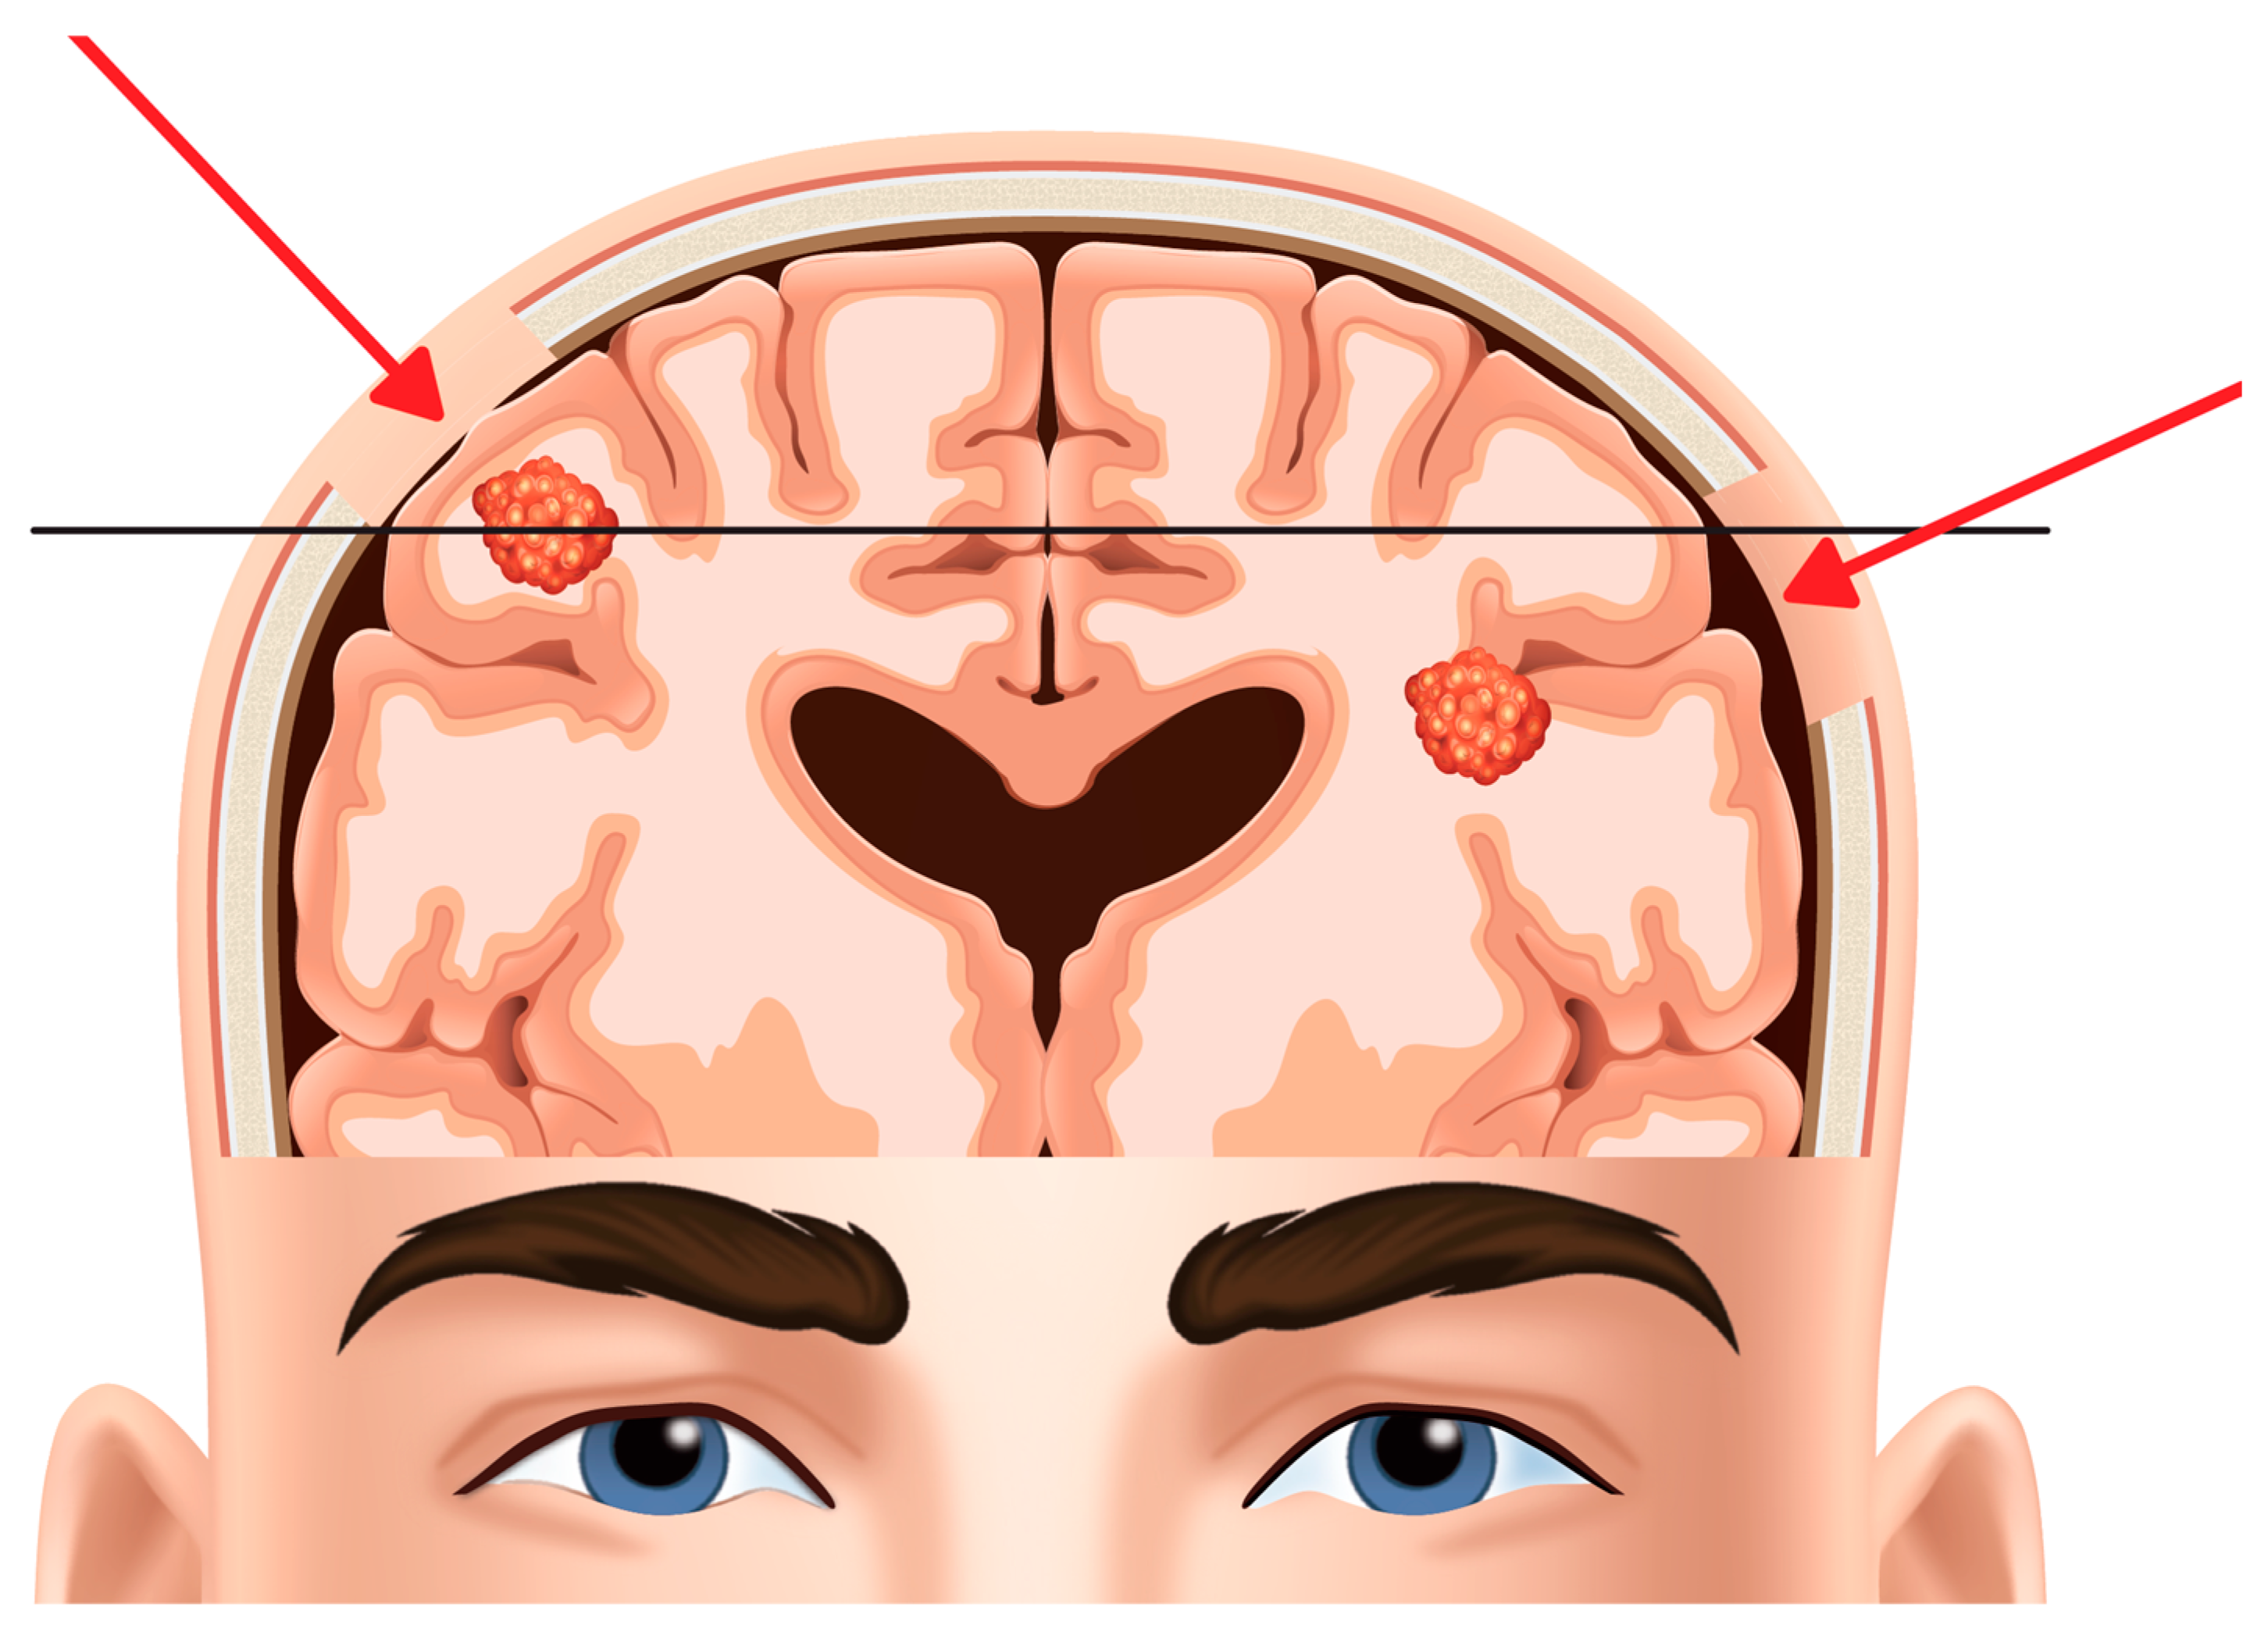

BM from solid extracranial neoplasms are the most frequent intracranial tumors, with an incidence up to 10 times higher than primary malignant brain tumors and which is steadily growing due to their early detection, ageing population, advances in neuroimaging and in the treatment of the systemic disease []. They are diagnosed in nearly 30% of patients harboring systemic solid tumors, mainly cancers of lung, breast and skin, but also renal cell carcinoma and gastrointestinal cancer. They typically occur at the grey-white matter junction in the brain hemispheres (75%), followed by cerebellum (21%) and brainstem (4%) [].

Two main resection techniques are commonly adopted, each carrying its own pros and cons: “en-bloc” resection which involves tumor removal in a single piece and “piecemeal” resection which involves excision in several small pieces. One or the other should be selected according to patient and pathology features.

The “en-bloc” resection technique, first described by Salvati et al. in 1996 [], involves removing the entire tumor as a single piece. It is performed by first obtaining the tumor subpial circumferential isolation through an initial corticectomy which is then followed by brain tumor dissection proceeding through deeper zones of brain parenchyma all around the tumor until reaching the bottom of the lesion. This method follows the principles of oncological resection decreasing the tumor cells spillage and minimizing blood loss, which bring a decreased risk of leptomeningeal dissemination [], postoperative complications and recurrence rates. In addition, it improves hemostasis, resulting in shorter operative time and less complications for highly vascularized metastases []. “Piecemeal” resection involves “getting into the tumor” and removing it in small pieces. It is obtained via internal debulking until regions of normal cortex and white matter appear. The main advantage of this technique is to preserve healthy brain and related neurological functions from injury. On the other hand, this approach may result in troublesome bleeding during resection which may reduce visualization and discrimination between vessels feeding the tumor and normal pial arteries and veins, making hemostasis more difficult and increasing the risk of iatrogenic ischemic injuries. During “en-bloc” resection, cortical landmarks are most readily identified prior to the start tumor resection which is performed at the gross boundaries of the lesion. Conversely, during the “stay within the tumor” technique, working from inside the tumor toward the functional cortex, the surgeon must decide when to stop the resection, balancing the risk of leaving residual tumor with the risk of causing iatrogenic injury to healthy brain tissue. As a corollary technique, “en-bloc” provides larger intact specimens for histopathology and research purposes, which results in more accurate diagnosis. Numerous studies attested the superiority of the “en-bloc” over the “piecemeal” technique of BM resection in terms of patients’ outcomes [,,]. Therefore, en-bloc should be the first choice when surgery is indicated in BM; nevertheless, the selection of which surgical technique to adopt depends either on patient-related factors, such as the their clinical condition and functional neuroanatomy but also on pathology related factors such as the histopathology of the primary disease. From the microscopic point of view, most BM are well demarcated, with variable perivascular growth (so-called “vascular cooption”) and/or a more diffuse infiltration (“pseudogliomatous” growth) in the adjacent brain parenchyma []; typically, they are circumscribed by a rim of gliotic tissue that separates the tumor from the surrounding healthy brain tissue which provides a safe dissection plane of resection.